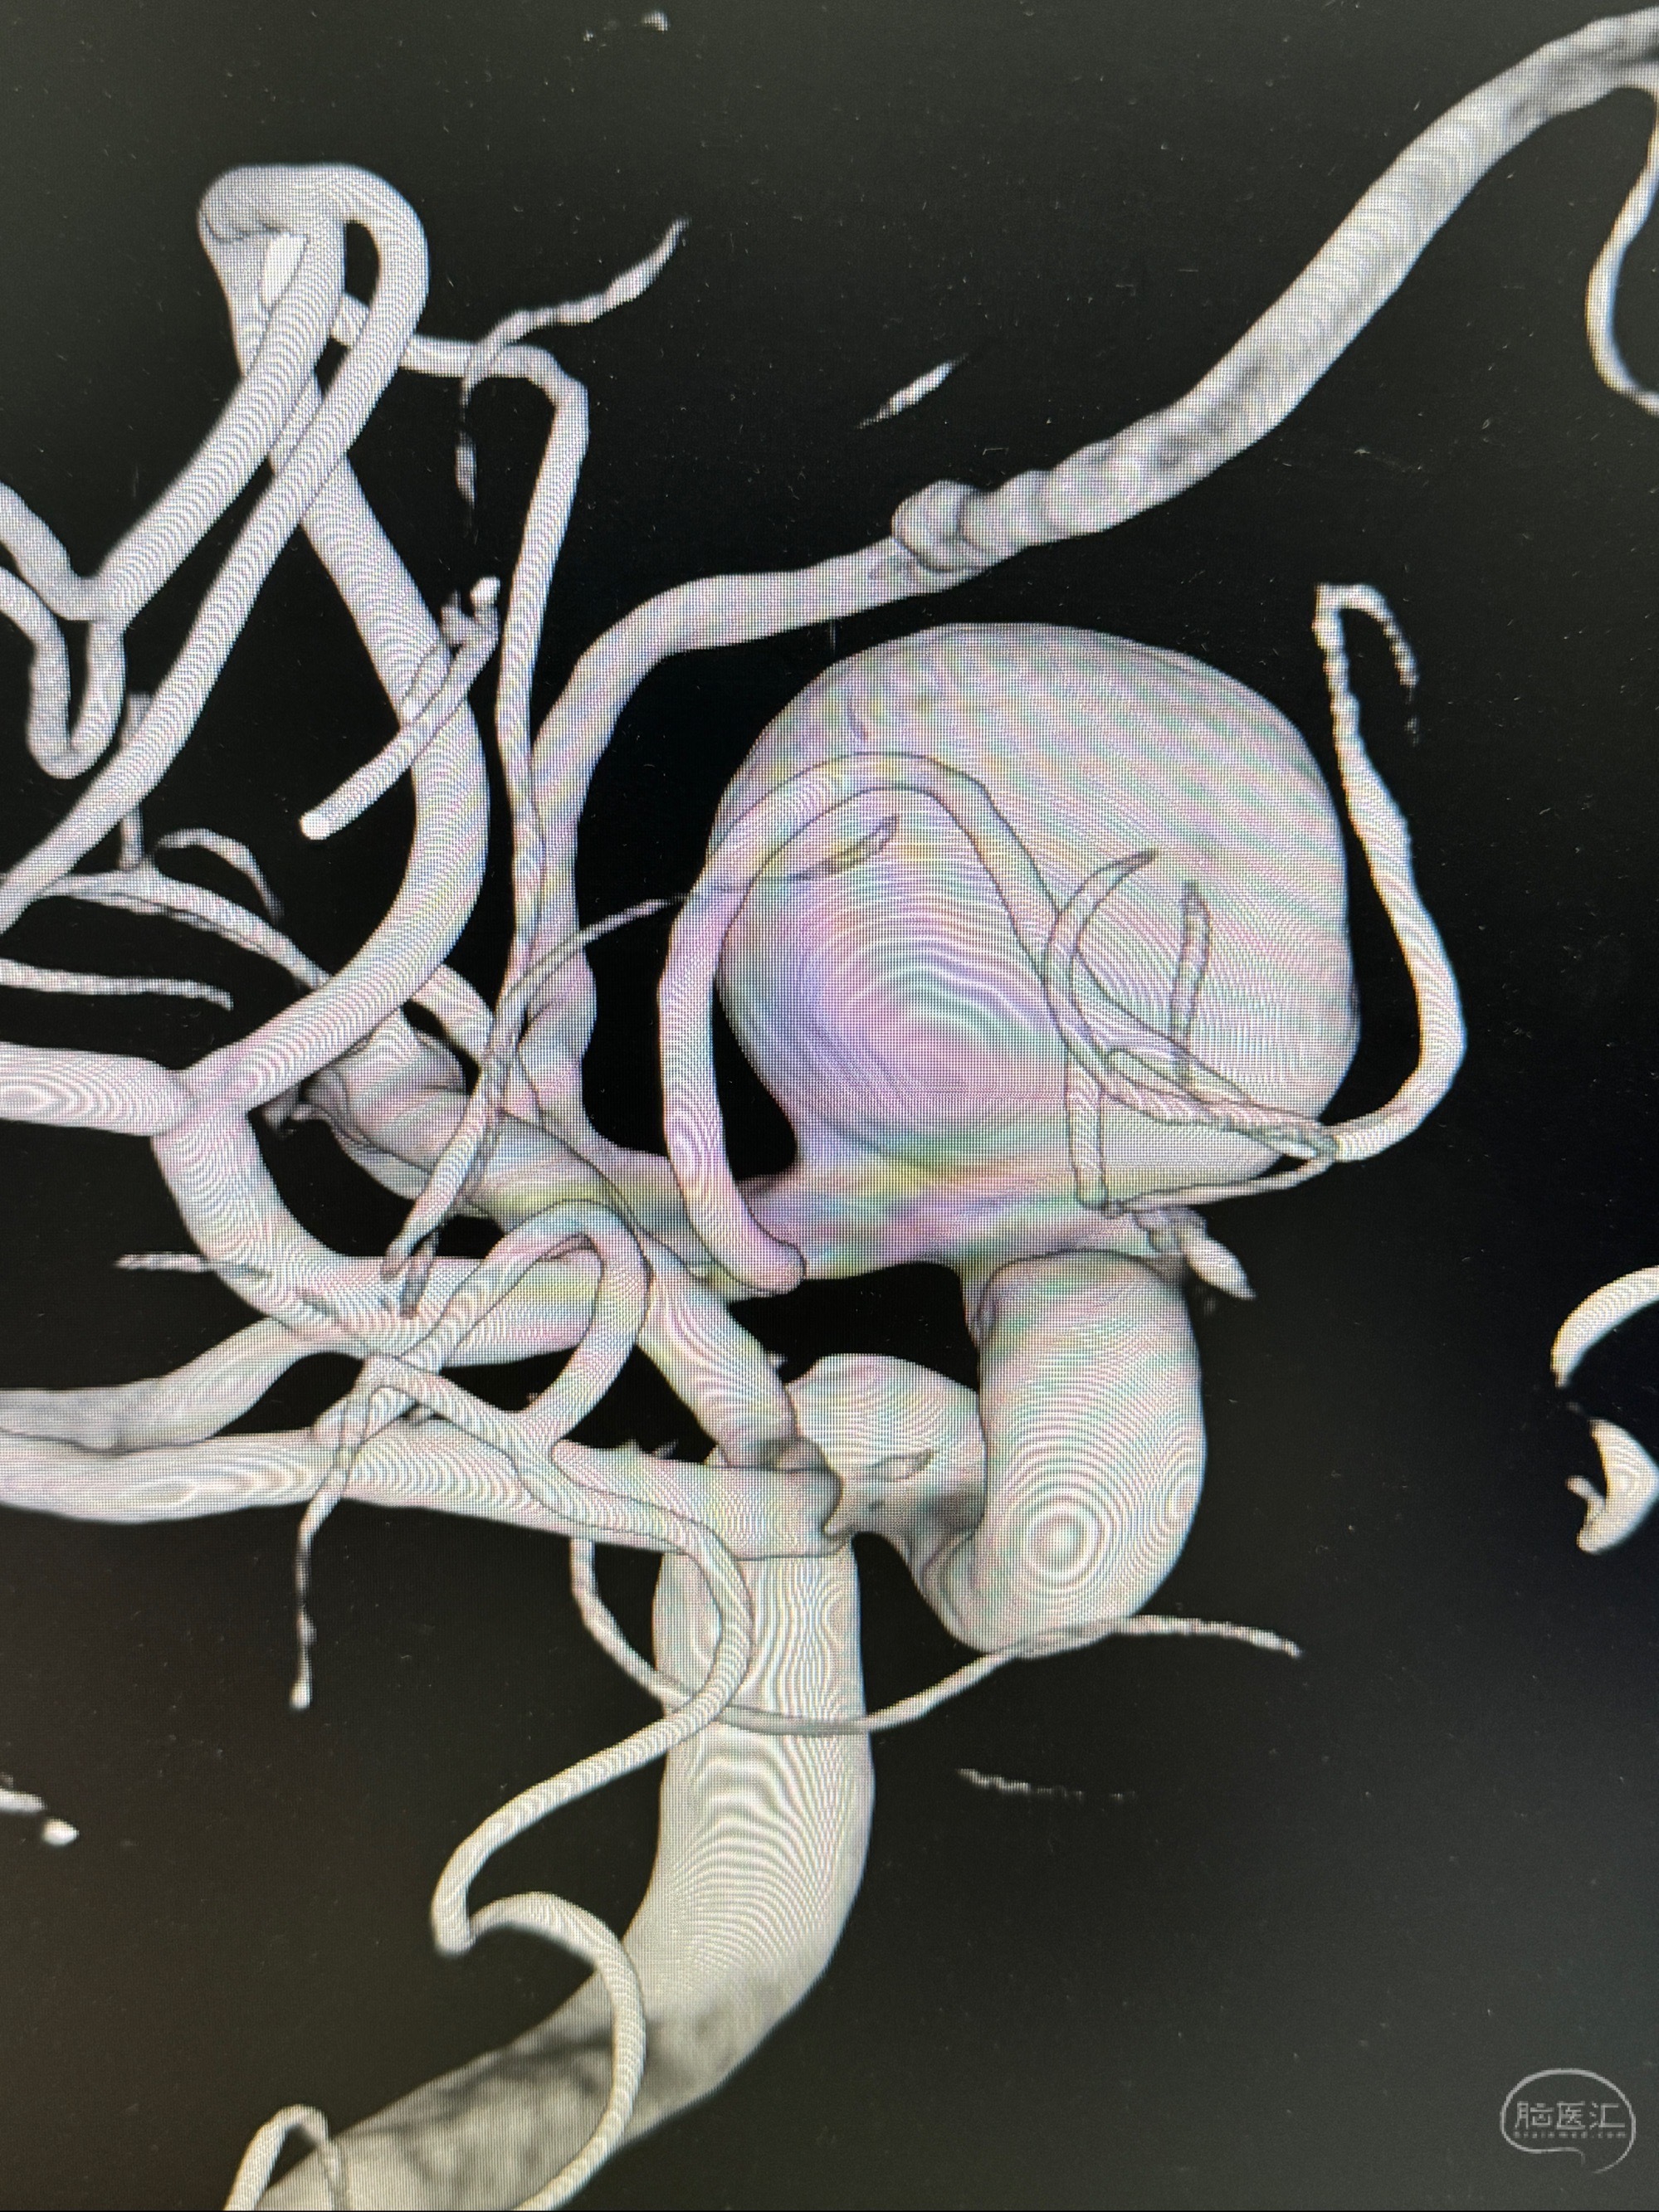

依次选取支架远段释放角度、动脉瘤近心段支架释放角度及瘤颈部切线位置

旋转3D展示动脉瘤局部的血管构筑

测量动脉瘤的大小:16*13.8*7.6mm大小,较原先变大,考虑双抗后瘤内血栓溶解可能

观察动脉瘤腔内的血流动力学情况

4.5-30mmTurbridge密网支架,于M1近心端打开

Tubridge 4.5-35mm

支架植入顺利,贴壁佳,支架内血流通畅,动脉瘤内血液滞留明显